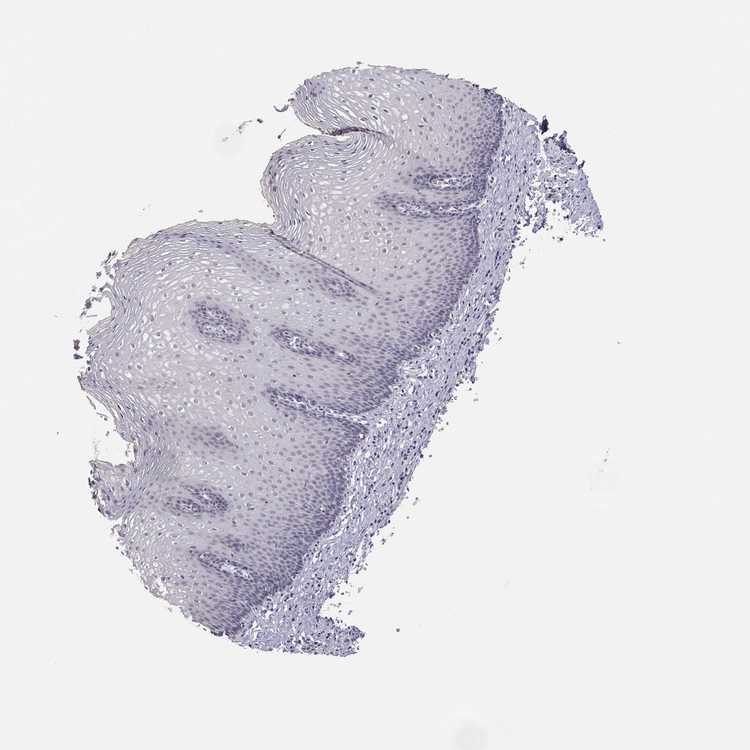

TISSUE PRIMARY DATA ESOPHAGUS Show tissue menu

ESOPHAGUS - Antibody stainingi

Antibody staining in the annotated cell types in the current human tissue is reported as not detected, low, medium, or high, based on conventional immunohistochemistry profiling in selected tissues. This score is based on the combination of the staining intensity and fraction of stained cells.

Each image is clickable and will lead to virtual microscopy that enables deeper exploration of all samples and also displays staining intensity scores, fraction scores and subcellular localization as well as patient and tissue information for each sample.